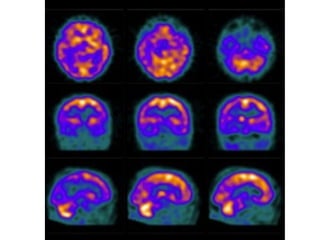

• SPECT: Hipofluxo parietal ou parietotemporal

• PET: com PIB, Pittsburgh compound B

• Hipoatividade frontal em SPECT

Fisiopatologia • Alteração neuroendócrina(redução da resposta ao TSH) • Redução da atividade serotoninérgica no núcleo da Rafe e redução de receptores 5HT • Redução da atividade noradrenérgica • Alterações vasculares • Degeneração de circuitos corticais e subcorticais de processamento afetivo e emocional. • Redução da atividade do Córtex préfrontal • Comprometimento do Núcleo Caudado e do Tálamo. • Hipoatividade frontal em SPECT